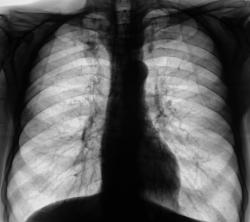

Контроль после флюорографии. Пациент давно снят с учета "у фтизиатра".

Пациент взят на "контроль" при расшифровке цифровых флюорограмм. Известно, что стоял на учете у фтизиатра. С учета снят 6 лет тому. Произведено стандартное рентгенологическое дообследование.

На 2 срезах очень похоже на туберкулому, и туберкулома не в спокойном состоянии.

Вполне спокойные туберкуломы.